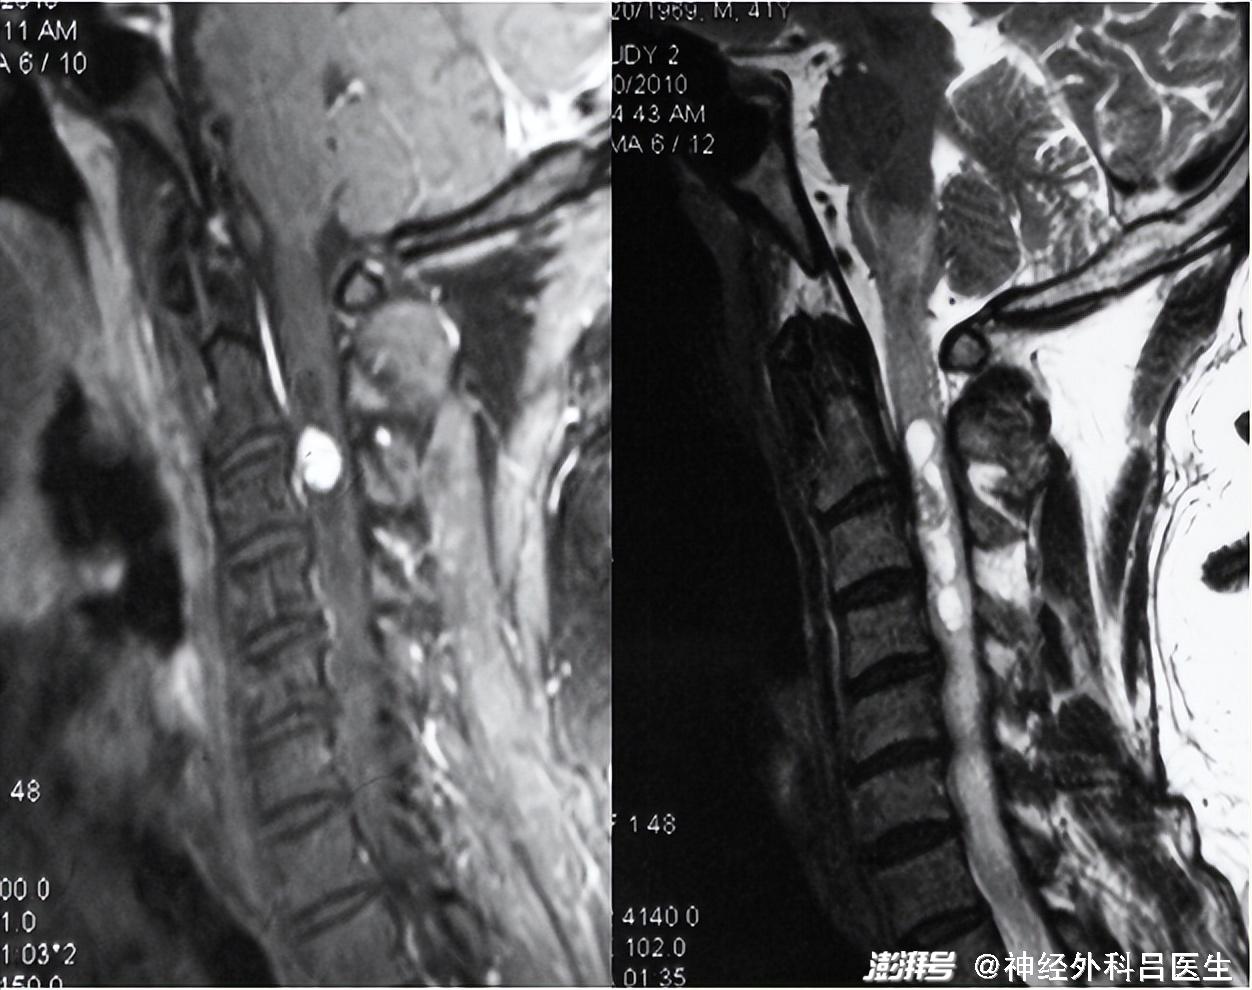

实性血管母细胞瘤及粗大的引流静脉MRI是诊断血管母细胞瘤最好的手段,可以准确显示肿瘤的位置、大小、形态,有无空洞和血管流空影。MRI T2加权像上可见瘤体内、肿瘤边缘和邻近区域不规则的点状或线状血管流空影,增强扫描肿瘤显著强化,呈极高信号强度,此为血管母细胞瘤的典型特征。囊性血管母细胞瘤多呈大囊腔小结节型,结节在MRI增强扫描时强化明显而囊壁不强化。MRI鉴别困难时,可利用血管母细胞瘤富血运的特征,借助DSA以协助确立诊断。另外,不同于其他椎管内肿瘤,脊髓血管造影对于血管母细胞瘤手术方案的制订也有重要价值。它可以显示肿瘤的供血动脉,引流静脉,能判定供血动脉的数目、部位、来源和方向,尤其是肿瘤和脊髓动脉的关系,保障手术的顺利进行。

脊髓血管母细胞瘤MRI特征性表现血管母细胞瘤属脊髓良性血管瘤,对放射治疗不敏感,手术治疗是最有效的根治手段。但因其血运特别丰富,且位于髓内,代偿空间狭小,所以手术难度较高,如操作不当则可产生严重后果。切除肿瘤前应先暴露阻断供血动脉,然后沿血管瘤的包膜小心分离四周,以小功率双极电凝反复电灼血管瘤包膜,缩小血管瘤体积,最后处理引流静脉,完整切除血管瘤。切忌分块切除或先阻断引流静脉,否则会引起难以控制的出血,模糊手术视野,又易损伤正常组织,增加手术难度。在电凝肿瘤包膜时应持续滴水以降低脊髓温度,防止热传导损伤脊髓。